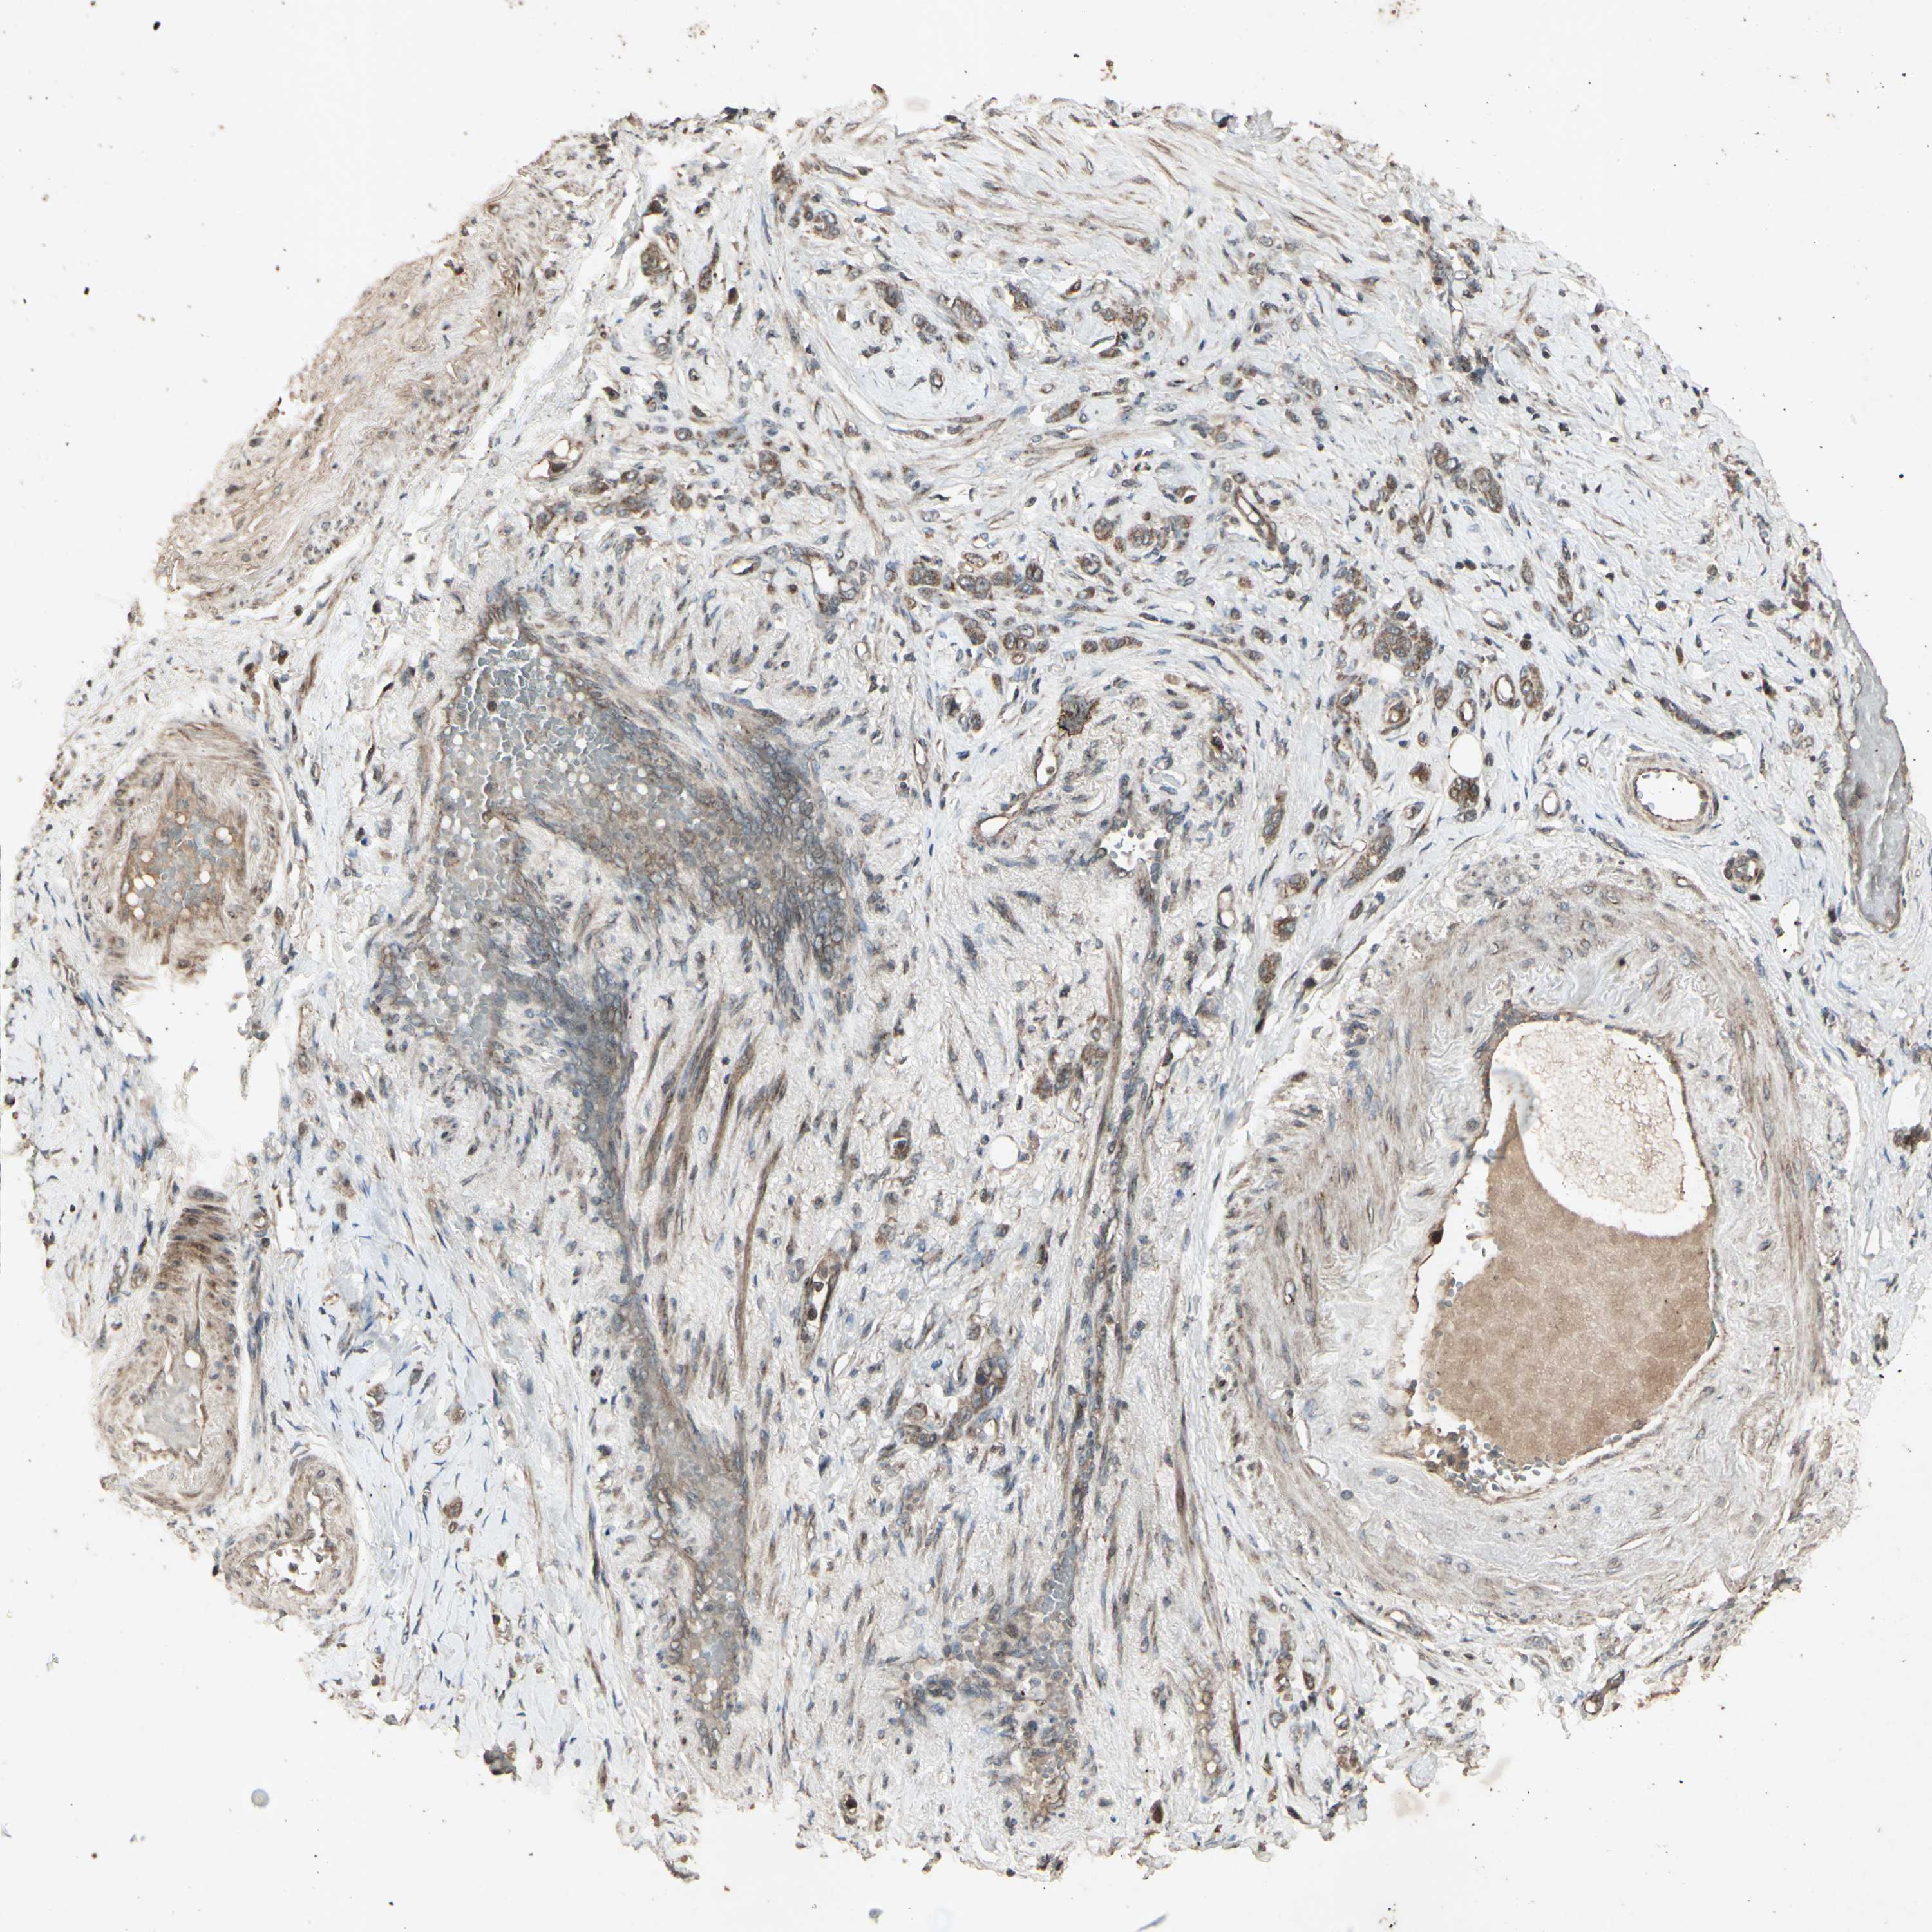

STOMACH CANCER - Protein expressioni

A mouse-over function shows sample information and annotation data. Click on an image to view it in a full screen mode. Samples can be filtered based on level of antibody staining by selecting one or several of the following categories: high, medium, low and not detected. The assay and annotation is described here.

Note that samples used for immunohistochemistry by the Human Protein Atlas do not correspond to samples in the TCGA dataset.

Antibody stainingi

Antibody staining in the annotated cell types in the current human tissue is reported as not detected, low, medium, or high, based on conventional immunohistochemistry profiling in selected tissues. This score is based on the combination of the staining intensity and fraction of stained cells.

Each image is clickable and will lead to virtual microscopy that enables deeper exploration of all samples and also displays staining intensity scores, fraction scores and subcellular localization as well as patient and tissue information for each sample.

Antibody CAB009049

Staining

High

Medium

Low

Not detected

Intensity

Strong

Moderate

Weak

Negative

Quantity

>75%

75%-25%

<25%

None

Location

Nuclear

Cytoplasmic/membranous

Cytoplasmic/membranous,nuclear

Adenocarcinoma, NOS

Adenocarcinoma, High grade